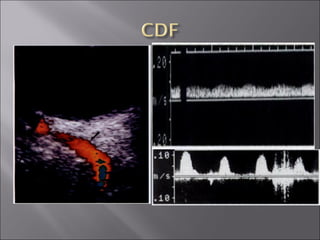

Ultrasound and CT scans provide anatomical images of the orbit, while color Doppler imaging provides visualizations of vascular structures and blood flow within lesions. These imaging techniques are used to evaluate a variety of orbital conditions involving blood vessels, infections, tumors, congenital issues, trauma, and more, and can help identify vascular disorders, thrombosis, treatment responses, and dynamic changes in benign tumors over time.